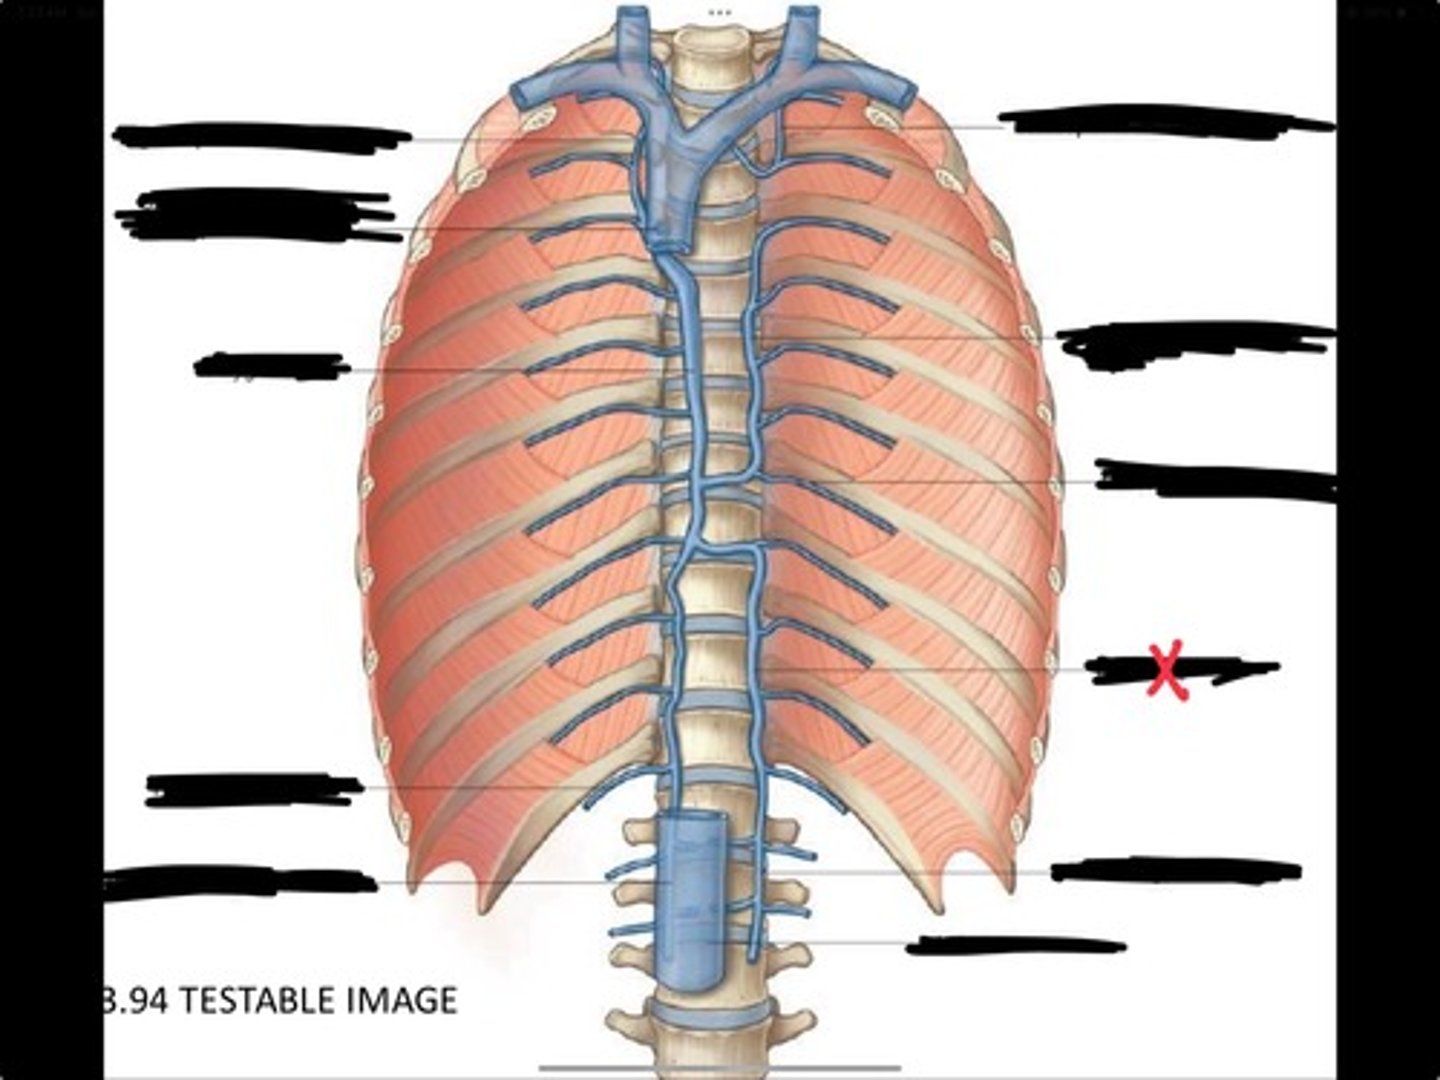

Right ascending lumbar vein

Right subcostal vein

Azygos vein

Opening of the azygos vein into superior vena cava

Right superior intercostal vein

Left superior intercostal vein

Accessory hemiazygos vein

Posterior intercostal vein

Hemiazygous vein

Ascending lumbar vein